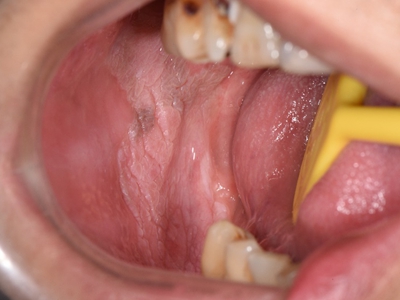

口腔

白斑

口腔白斑病口腔下面黏膜白斑图

口腔白斑病表现为口腔黏膜有白色皱纸样的斑块,基底柔软,与正常黏膜的边界清晰,覆盖大半个左侧下嘴唇,患处有木涩感,有时会感到疼痛。